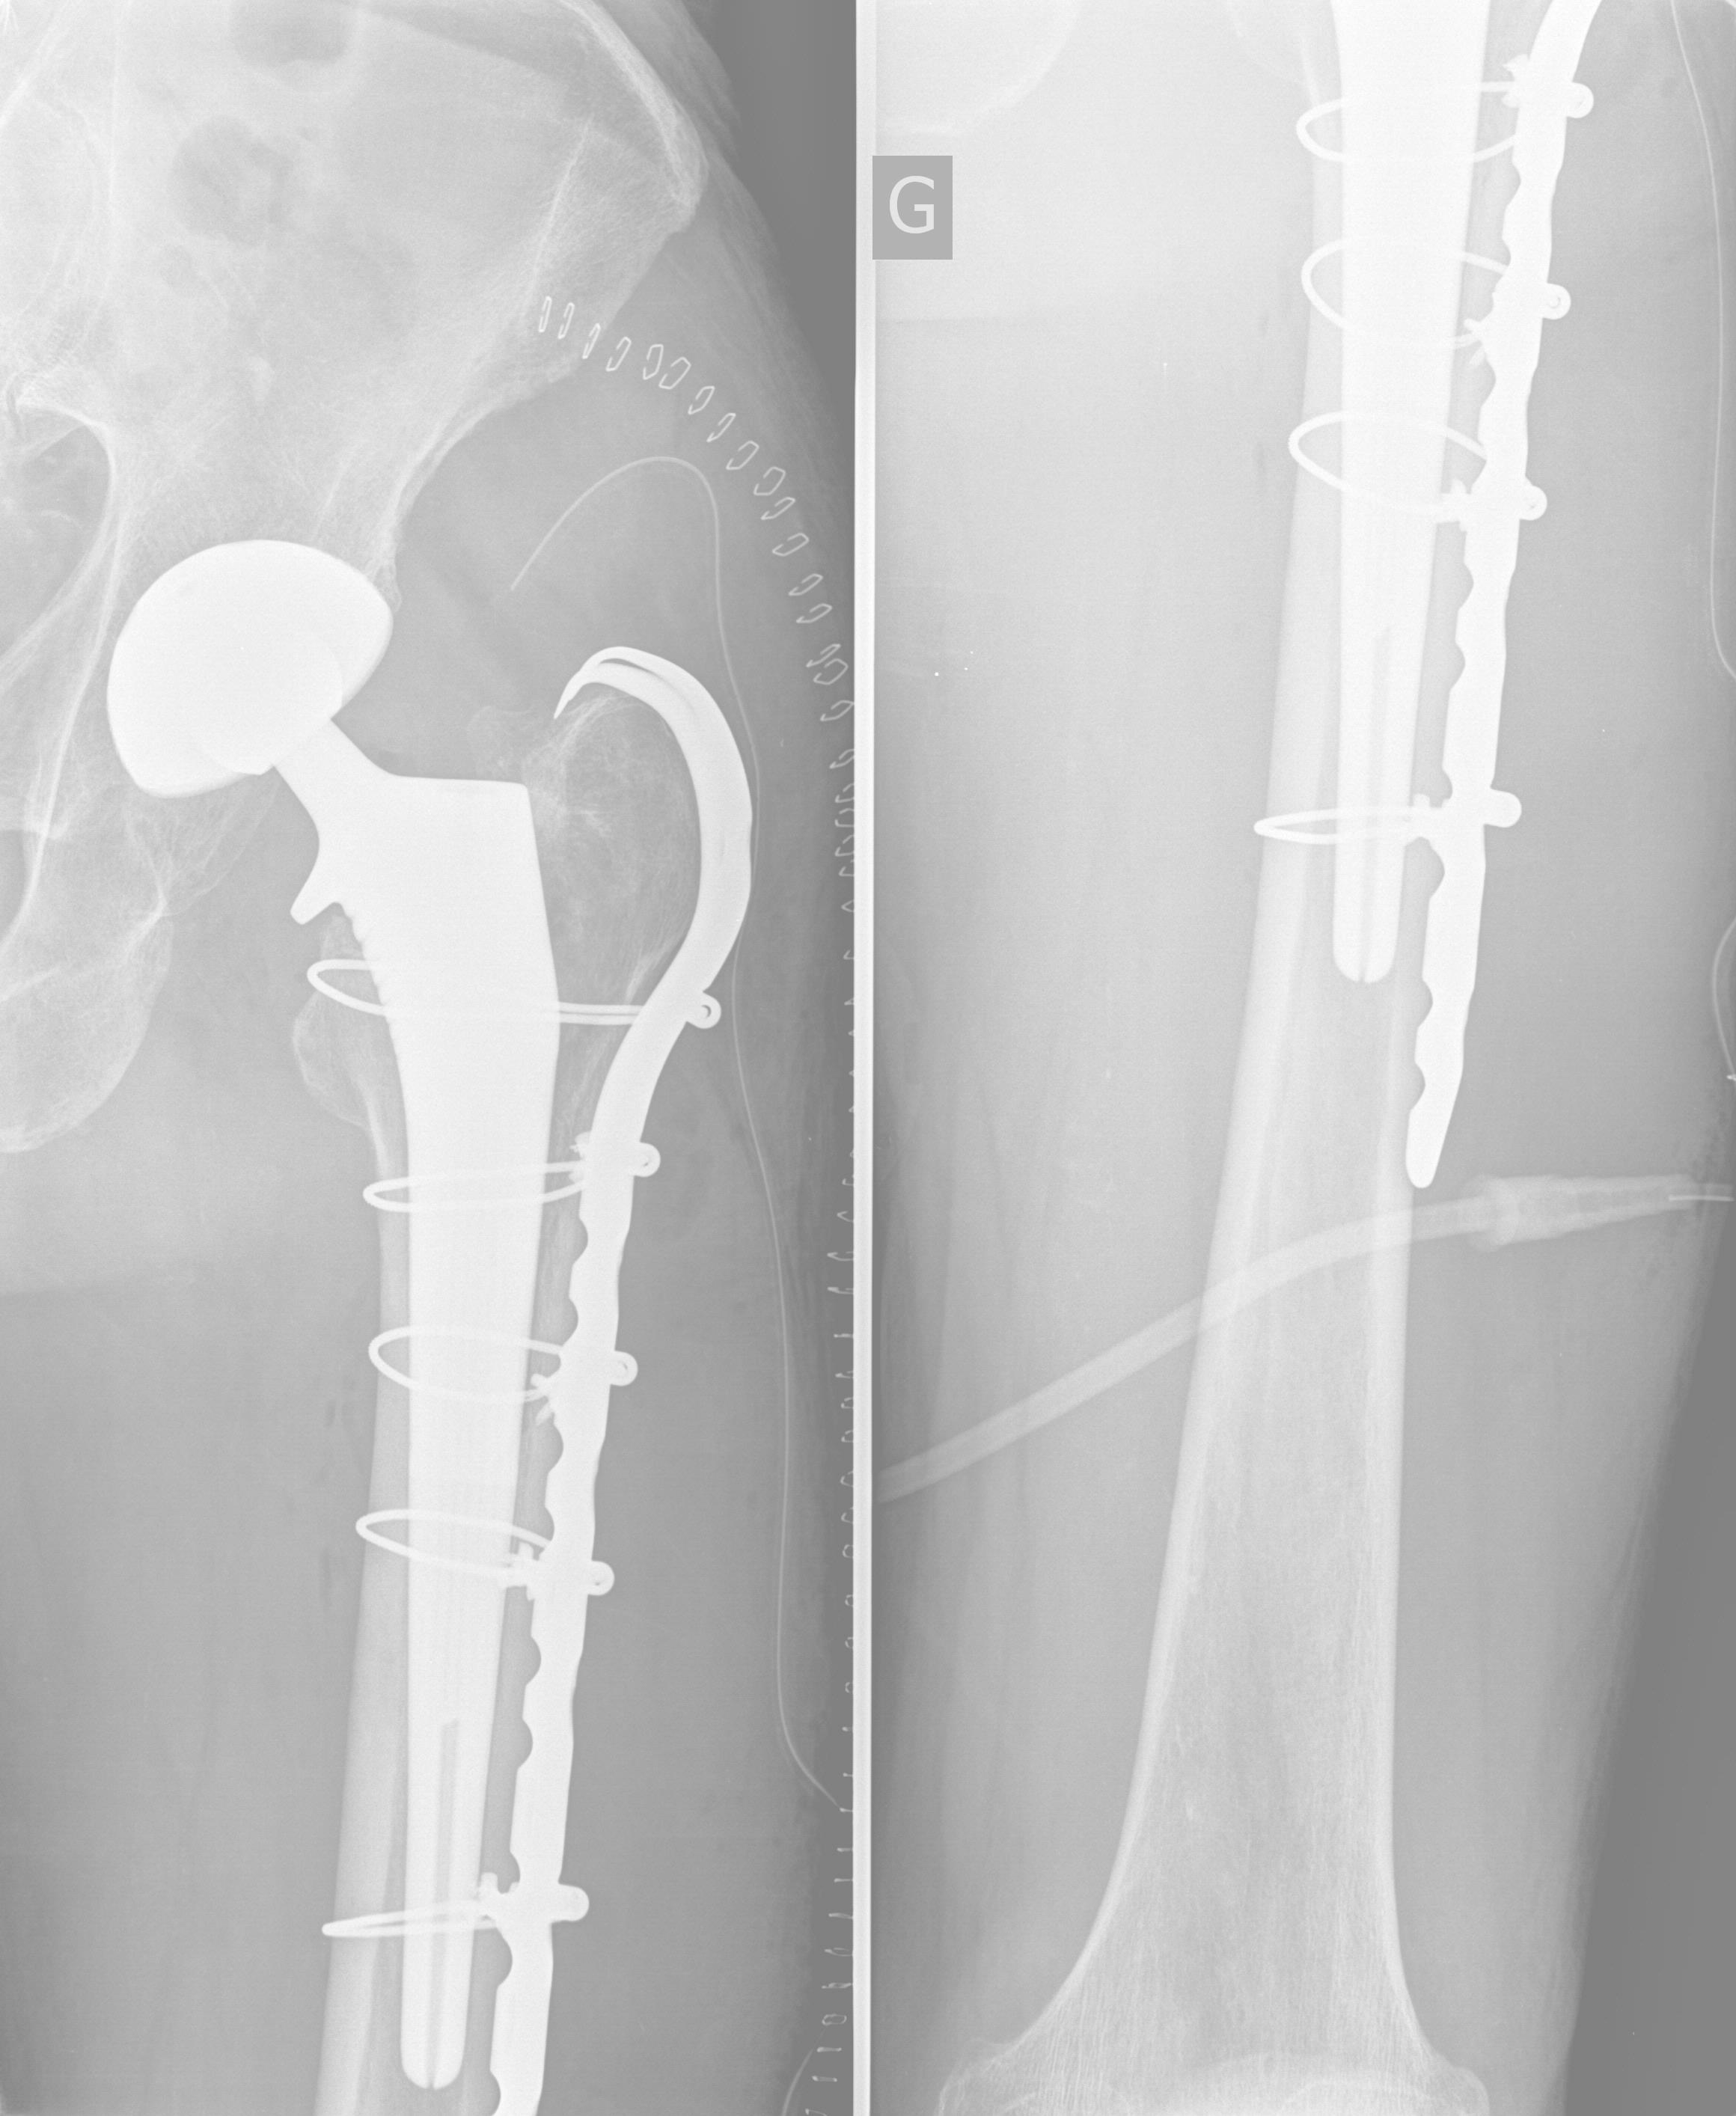

Moi aussi j'ai des souvenirs du Brésil d'octobre 2016 ![]() Là je venais de dégueuler dans l'ambulance ![]() ![]() Ici c'est l'infirmerie de Paraty ![]() Ma place dans un vol Air France ![]() Ma place à l'hosto à Bruxelles ![]() Et mes souvenirs. ![]() ![]()